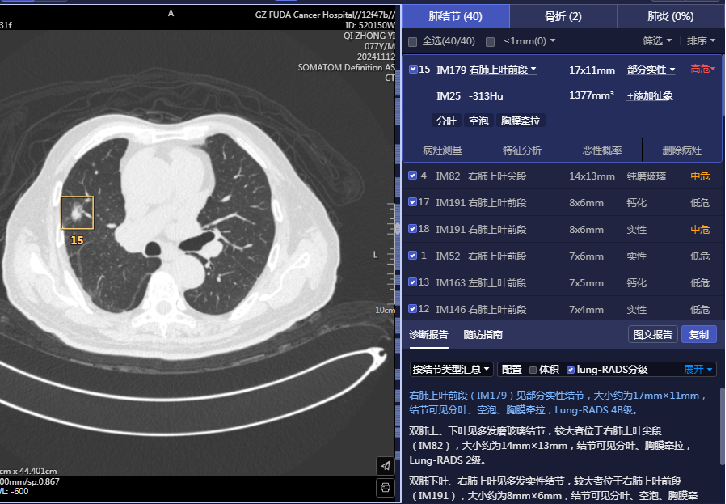

在發(fā)現(xiàn)疑似病灶后,系統(tǒng)會自動快速定位可疑病灶區(qū)域,用色框清晰標注小結節(jié)坐標提示醫(yī)生,并對結節(jié)的可疑病灶數(shù)、性質(zhì)、直徑、體積、CT值等信息以及影像學表現(xiàn)進行描述,醫(yī)生就可以對這些有問題的地方著重處理,為后續(xù)治療方案的制定提供了關鍵依據(jù)。

03 鑒別良惡,精準診斷

憑借強大的數(shù)據(jù)分析能力,AI可以深度剖析結節(jié)的各種特征,并結合豐富的臨床信息,在良惡性鑒別診斷上表現(xiàn)卓越。如:快速給出良惡性判斷及其惡性風險分級,提高診斷效率的同時,還能突顯結節(jié)圖像中的可疑征象,并實時呈現(xiàn)給臨床醫(yī)生,為結節(jié)的分類診斷提供重要參考依據(jù),從而有利于降低誤診率,避免了患者不必要的擔憂和過度治療。

▲患者77歲,男,右下肺切除術后12年余,發(fā)現(xiàn)右上肺結節(jié)2年余;直腸癌、膀胱癌綜合治療后。完善相關檢查AI提示右上肺結節(jié)為高危,結合既往病史,我院為其施行右肺結節(jié)經(jīng)皮穿刺細胞學涂片+冷凍消融術,右肺結節(jié)細胞學檢查示:送檢(右肺)細針穿刺細胞學涂片中查見癌細胞。